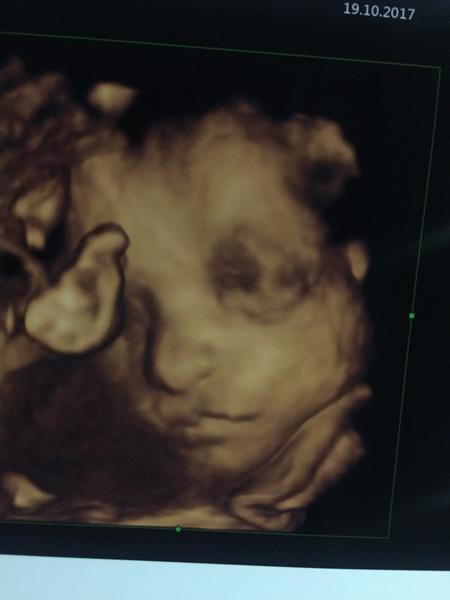

Dievcence idem vás trosku povzbudiť. Nám sa v gynfive pred viac ako ôsmimi mesiacmi zadarilo a budúci týžden ma čaká pôrod. Nebol to prvý pokus, bolo ich viac, ale nakoniec sme to dotiahli až sem a o chvíľku uvidíme našu princeznú 😍